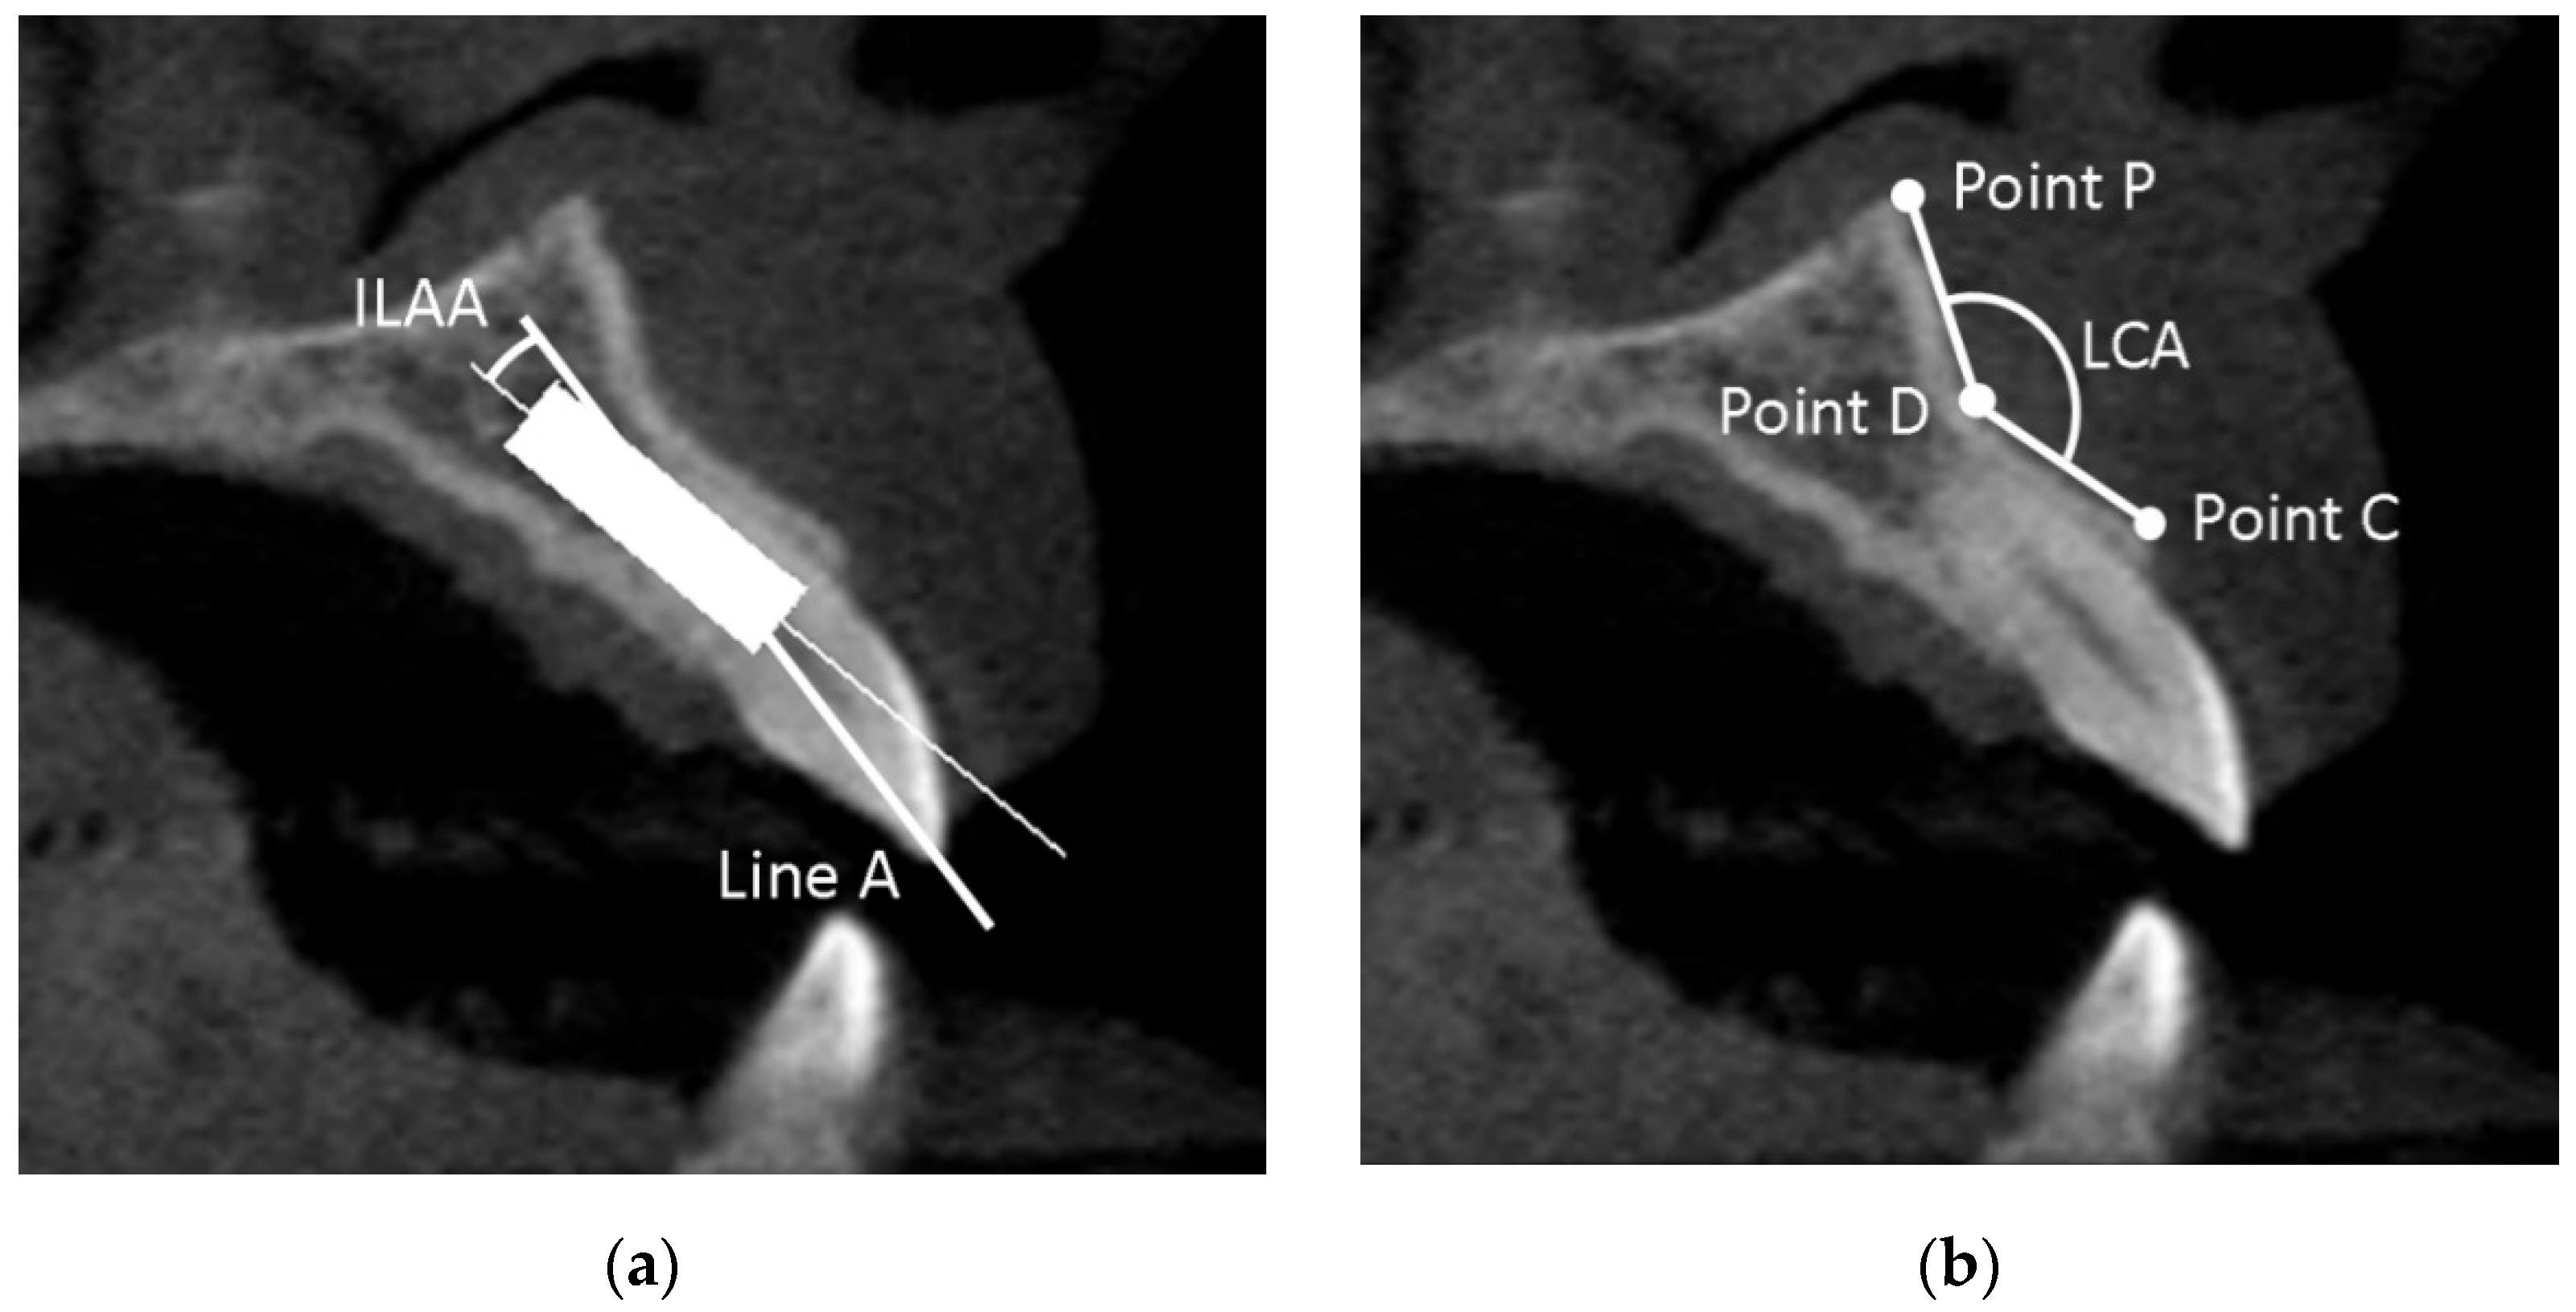

The angle between the prosthetically-driven ideal position (line A) and the long axis line of the implant in bone-driven position was determined, and defined as the implant-line A angle (ILAA) (Figure 2a).

Figure 2.

(a) The implant-line A angle (ILAA); (b) the labial concavity angle (LCA).

2.6.5. Labial Concavity Angle (LCA)

The LCA was defined as the angle between the line D–C and the line D–P (Figure 2b). Point C was defined as the most coronally external point of the labial plate, point D as the most internal point, and point P as the most external apical point of the labial plate superior to point D.